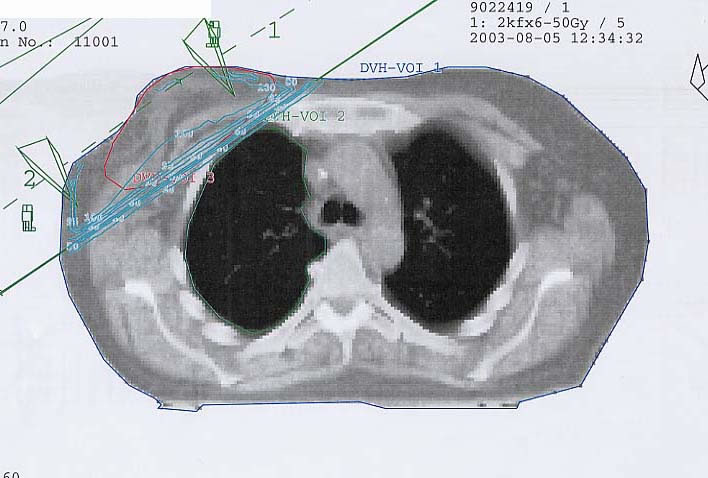

Mammakarzinom: Bestrahlungsplan

Bestrahlungspläne